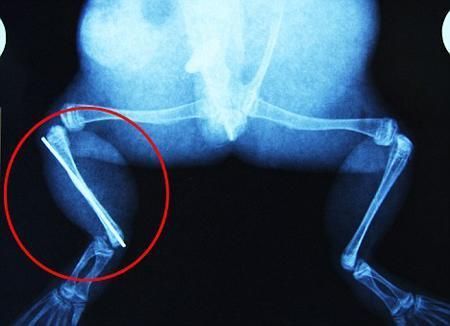

布魯萊的主人,居住在南非約翰內(nèi)斯堡附近的62歲的安妮·米恩斯說:“我對這只青蛙如此關心,人們一定認為我瘋了,但是我無法眼睜睜看著它那么痛苦。青蛙因其靈活的腿腳而著稱,一想到布魯萊的腿里要留下一個薄金屬片,我就感到心痛。然而我知道,如果不進行手術,布魯萊以后就沒辦法動彈了。因此我匆匆趕到獸醫(yī)那里,央求他給這只可憐的青蛙動手術。這位獸醫(yī)整天救助小貓小狗,他很難理解為什么我這么擔心一只青蛙,但是最終他還是答應了給布魯萊做手術。手術后是幾個小時的焦急等待,我們希望它能快快蘇醒過來。不過現(xiàn)在它的傷口已經(jīng)愈合,又能在花園里跳來跳去了。X光照射顯示,它會恢復的跟以前一樣。”

野生生物專家安妮經(jīng)常為學校寫教材,她認為這是人類第一次通過手術給一只青蛙接斷腿。在手術開始階段,獸醫(yī)把少量給狗用的麻醉藥注入到這只青蛙體內(nèi),讓它失去知覺。然后他在布魯萊的斷腿上切開一個小口,把一根小鋼針植入腿里。最后獸醫(yī)給它縫了9針,把切口縫合在一起。僅僅幾周后,布魯萊就能在安妮家附近活動了。這只青蛙大約已有25歲,主要以嚙齒動物、蛇和其他青蛙為食。布魯萊所屬的牛蛙種群正在不斷減小,目前只能在非洲南部的濕地里才能看到這種青蛙。

安妮有2個孩子,她已經(jīng)從事20多年兩棲動物保護工作。她認為鄰居家的狗狗在把布魯萊從地下刨出來的時候,它正在地下冬眠、她說:“世界上只有這個地區(qū)能看到這種牛蛙,這種青蛙現(xiàn)在變得越來越稀少。因為我從事野生生物保護工作,因此認識很多兩棲動物專家,但是以前他們誰也沒見過這種事情。看到布魯萊越來越健康我非常開心。現(xiàn)在還需要一段時間,它的金屬腿和它的骨骼才能融為一體,那時布魯萊會跟以前一樣健康。我們認為這個過程需要幾周時間,但是一旦它完全康復,我希望把它放歸大自然,讓它重新回到它最鐘愛的濕地里。”